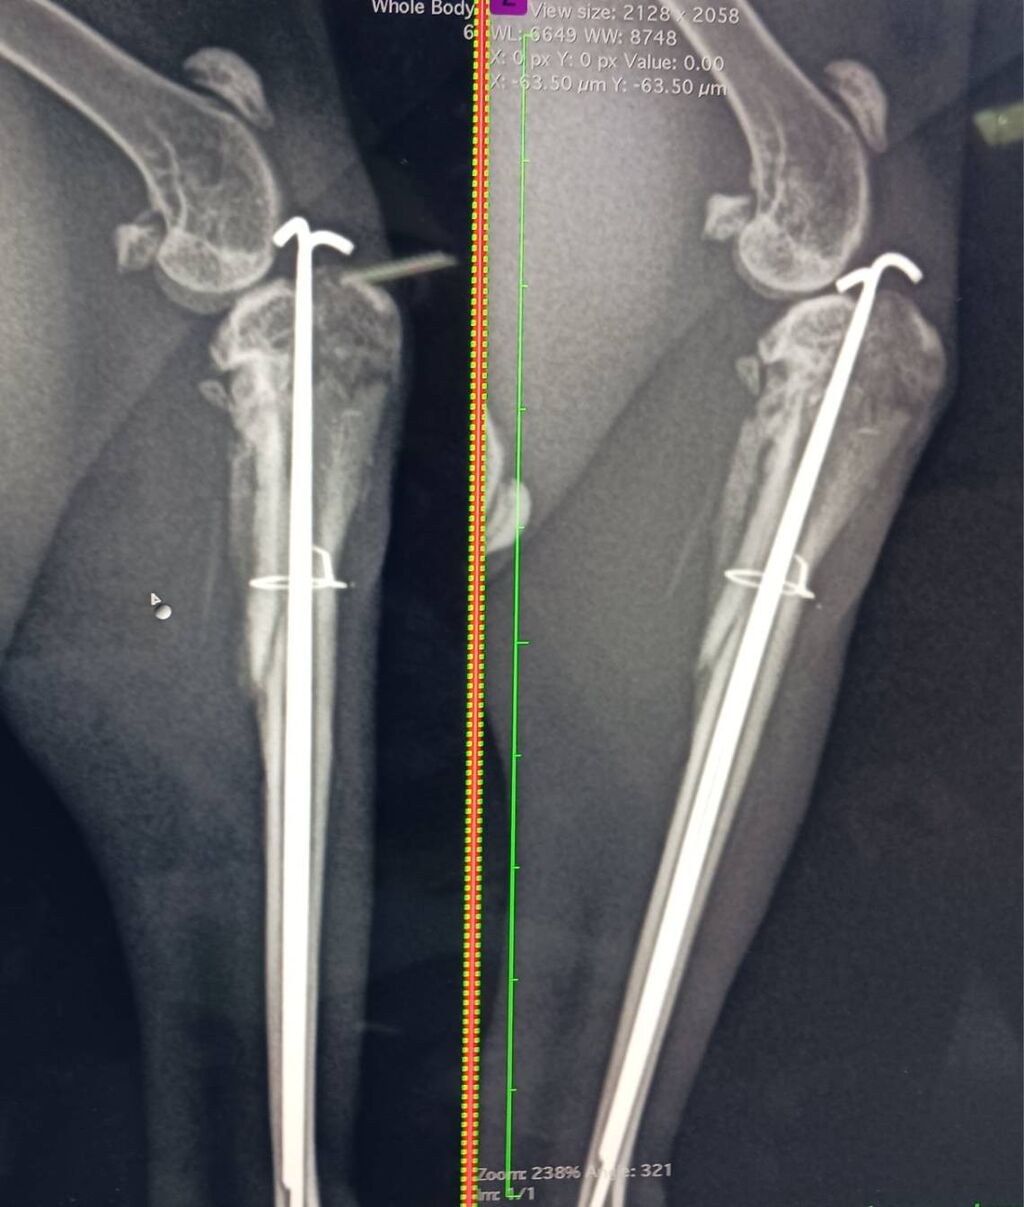

2025年11月に右後ろ脚を骨折し、11/14にピンニング手術を受け、現在も経過観察中です。

12/5 経過を見るために受診しました。

骨の再生がほとんど見られず、経過は想定より厳しい状況との説明を受けました。

後方2か所にわずかな骨量の増加は見られるものの、2か月経過しても反応が乏しい場合は、ピンを留置したままの経過観察、再手術、または断脚も選択肢になるとのことでした。

右後肢は力が入りにくいものの、痛みの反応はあり、神経は保たれている可能性が高いとの見立てでした。

今後は足を使う機会を増やし、2〜3週間後に再度レントゲンで確認する予定となりました。

12/19 経過を見るために受診しました。

骨の再生が少しずつ進んでいることが確認できました。

左かかとにソアホックはなく、右後肢の筋肉量は落ちているものの、前回と比べ大きな悪化は見られませんでした。

足を浮かせる原因については、ピン挿入による違和感や、受傷時の筋肉・神経・靭帯への影響などが考えられるものの、判断は難しいとのことでした。

右目周囲の油分残りについては、ケアのしにくさが影響している可能性もあり、引き続き経過観察となっています。

厳しい状況が続いていましたが、少しずつ前向きな変化も見られています。

時間はかかっても、はるくんのペースで回復につながるよう、引き続き慎重に見守りながらケアを続けていきます。